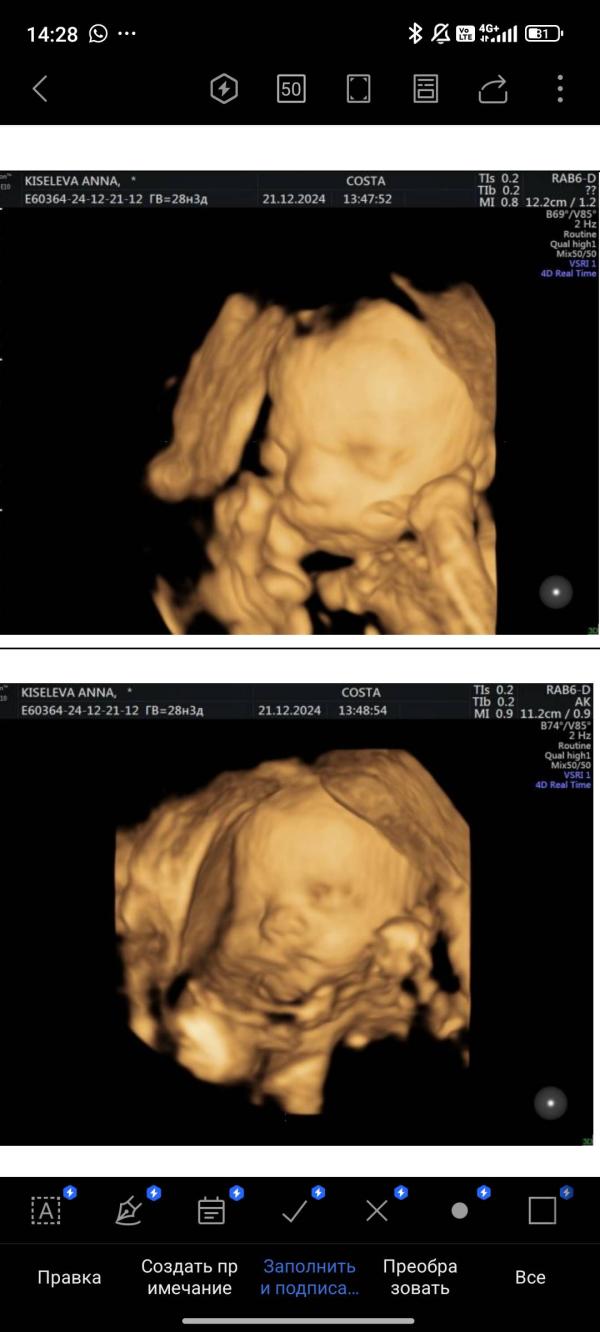

Ах да за пару дней до теста сходила на узи т.к. очень переживала что ковид мог отразится на малыше или кровотоках и тонус стал мучать при хотьбе. Но ттт всё идеально, еле как сфоткали его сладкие щёчки 🥰